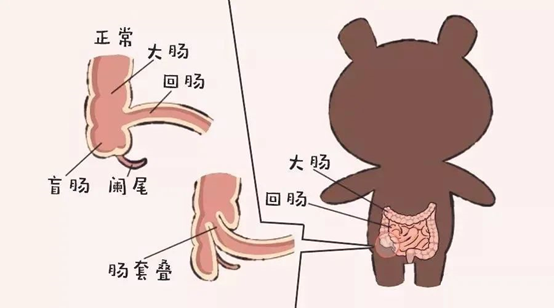

肠套叠是临床上最常见的小儿急腹症之一。发病年龄多在2岁以内,主要集中在6~12个月龄婴儿。男孩发病率比女孩高,男女发病率之比为2~3:1。分为原发性肠套叠与继发性肠套叠,婴儿肠套叠几乎均为原发性,原发性肠套叠按其部位分为四型,分别是回结型(占85%)、小肠型(占6%~10%)、结肠型(占2%~5%)、回回结型(占10%~15%),原发性肠套叠的发病因素包括免疫反应不完善、饮食结构改变、肠炎、病毒感染等。继发性肠套叠发病因素常见Meckel憩室、肠息肉、肿瘤、过敏性紫癜等。

原发性肠套叠多见于肥胖健壮的婴幼儿,典型的临床表现如下:

(4)、腹部包块:肠管发生套叠,在哭闹的间歇期,多在右上腹或脐上会出现长条的包块物。